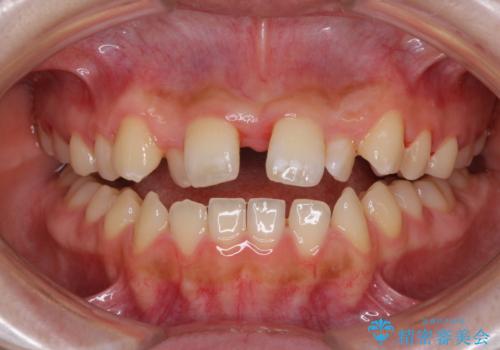

- 前歯のデコボコと、下顎の変位と受け口を気にして来院された患者様です。

初診時には大学病院にて顎の骨を切る外科矯正を勧めましたが、妥協的なゴールでも構わないので外科処置をせずに矯正を行いたいとのことでした。

まずは急速拡大装置にて上顎骨を側方に拡大し、インビザラインにて歯列と咬合を整えることとしました。

上顎骨を拡大したことで、下顎の歯列を上顎が受け入れられるようになりましたが、インビザラインでは咬み合わせを改善させることができなかったため、ワイヤー矯正にて仕上げることとしました。

ワイヤーを使用したものの、上下前歯のオープンバイトがなかなか改善されませんでしたが、患者希望により治療終了となりました。